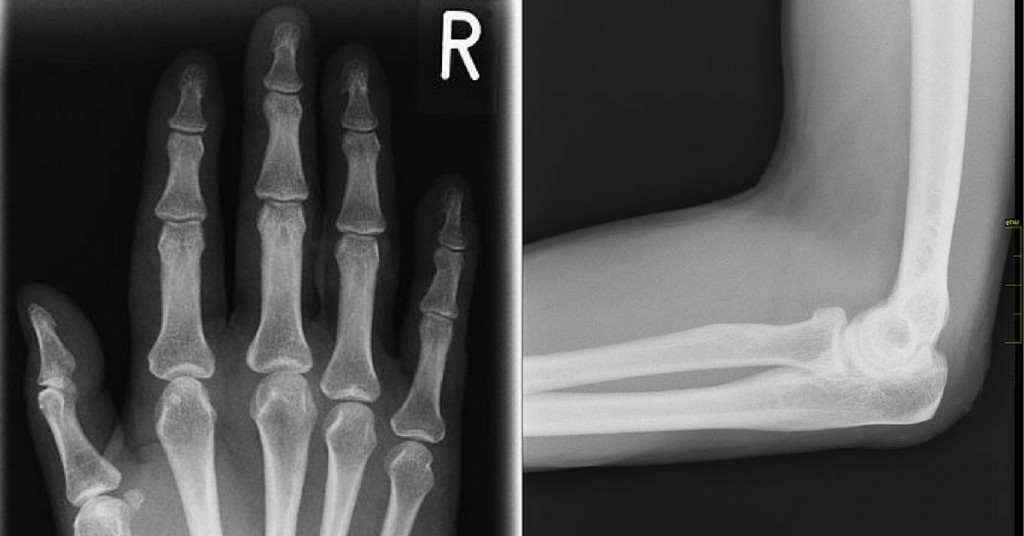

Knocking your funny bone on something certainly isn’t laugh-out-loud funny. The name references another kind of funny: You feel funny when it happens—a specific kind of jolting nerve pain that spreads throughout the whole body for just a second. (The common phrase “Tickle your funny bone” just complicates things unnecessarily.) Oh, and the funny bone isn’t really even a bone. Hitting it on a wall or door sends weird (okay, funny) nerve pain throughout the body because it is a nerve. It’s the ulnar nerve, and the pain comes from it getting pinched under a bone. And that bone is the long, elbow-to-shoulder spanning one called the humerus, pronounced humorous, which could also be why the funny bone is called what it is.